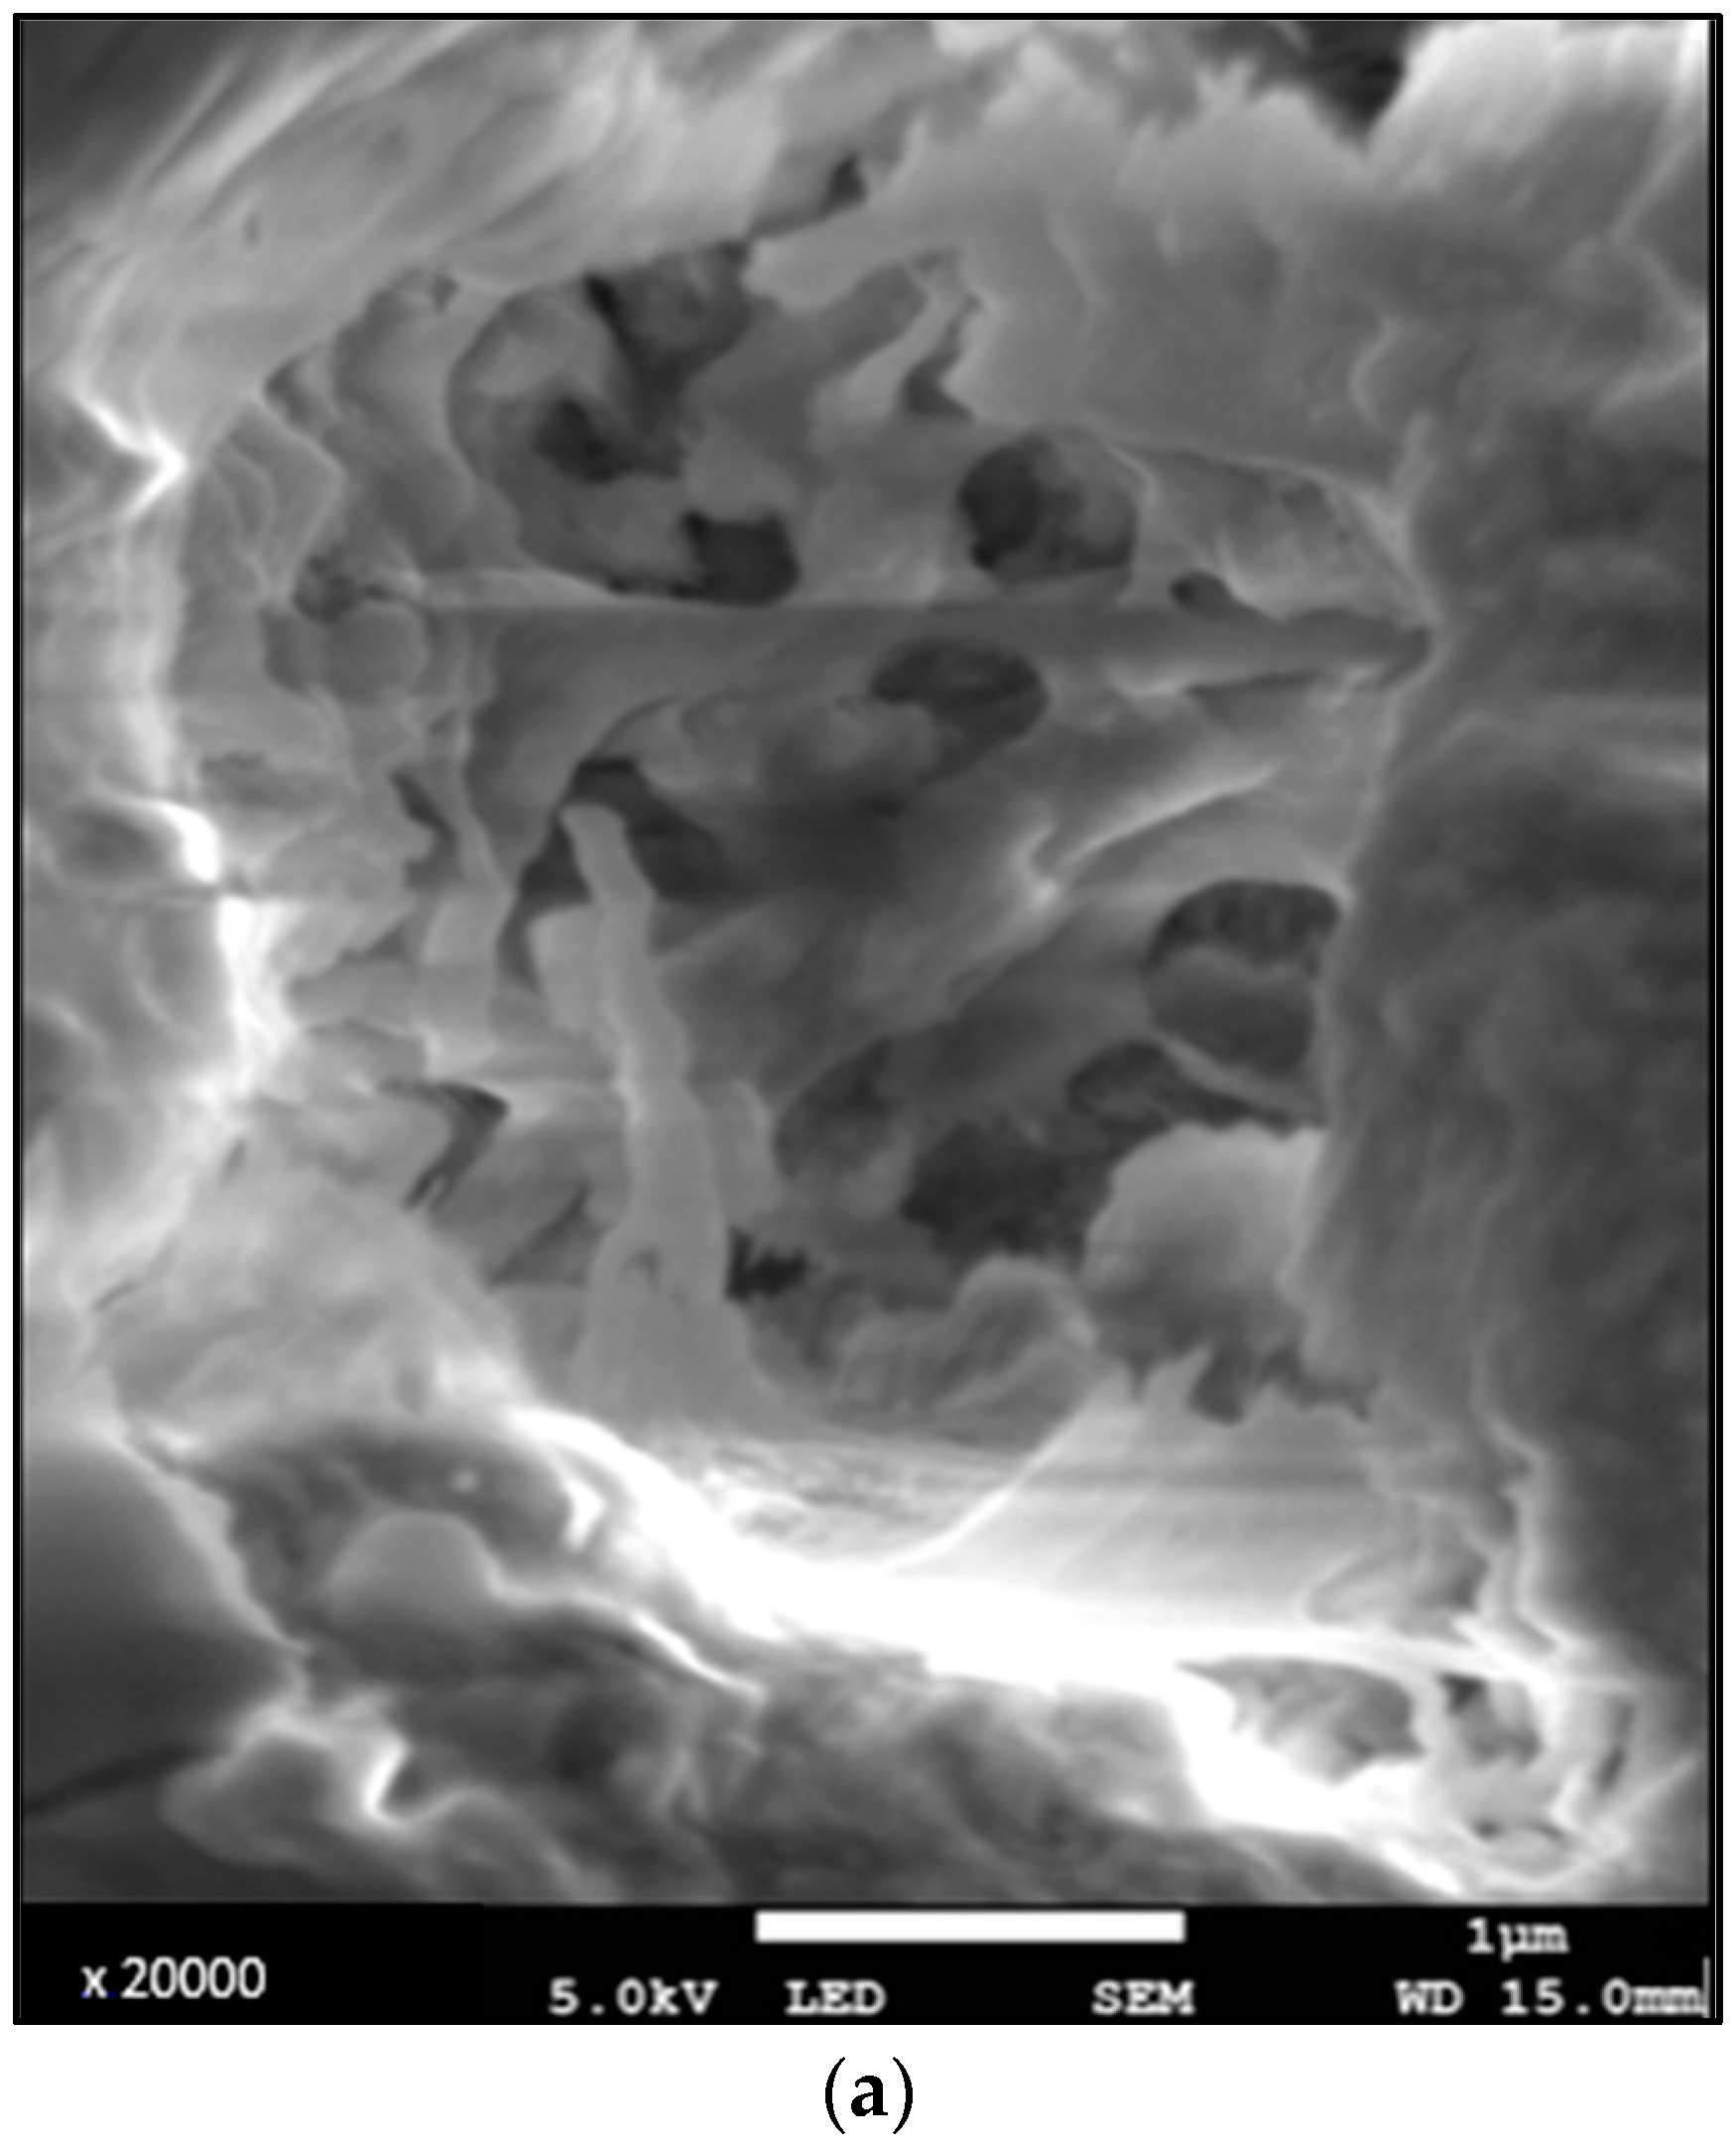

- Appearance of sclerotic dentin and tubules